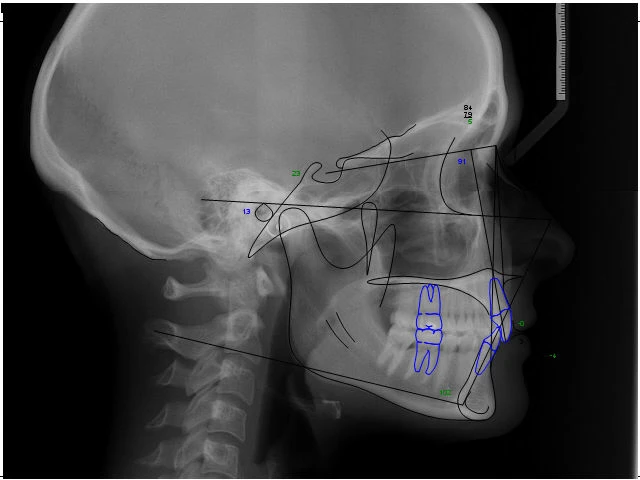

Đọc tiếpKỸ THUẬT TRACING Thực hiện tracing cần theo một hệ thống. Đầu tiên nên bắt đầu bằng việc kiểm tra…